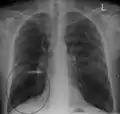

انجام رادیوگرافی قفسه سینه و شمارش کامل خون ممکن است در زمان تشخیص، احتمال ابتلا به شرایط دیگر را از میان بردارد.[49] نشانههای مخصوص در رادیوگرافی شامل گشاد شدن ششها، دیافراگم صاف، فضای خالی افزایش یافته پشت جناغ و آبکیسه میباشد، این در حالی است که میتواند بیماریهای ریوی دیگر مانند سینهپهلو، اِدِم ریه یا پنوموتوراکس را شامل نشود.[50] اسکن رزلوشن بالای توموگرافی رایانهای از سینه ممکن است پخش آمفیزم در ریه را نشان دهد و میتواند احتمال ابتلا به بیماریهای ریوی دیگر را از میان بردارد.[2] این مورد، غیر از مواقعی که عمل جراحی انجام شدهاست، به ندرت بر مدیریت بیماری تأثیر میگذارد. فشار گاز خون شریانی برای تعیین نیاز به اکسیژن استفاده میشود و برای افرادی که FEV1 آنها کمتر از ۳۵٪ پیشبینی شدهاست، افرادی که اشباع اکسیژن خون آنها کمتر از ۹۲٪ است و افرادی که علائم نارسایی احتقانی قلبی دارند توصیه میشود. در مناطقی از جهان که نقص آنتی تریپسین آلفا-۱ شایع است، باید از افراد دچار COPD (مخصوصاً افراد زیر ۴۵ سال که آمفیزم روی قسمتهای تحتانی ریههایشان اثر گذاشتهاست) آزمایش گرفته شود.[8]

Chest X-ray demonstrating severe COPD. Note the small heart size in comparison to the lungs.

A lateral chest x-ray of a person with emphysema. Note the barrel chest and flat diaphragm.